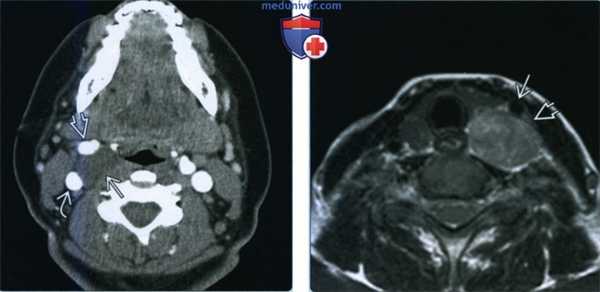

(Слева) КТ с КУ, аксиальная проекция. Образование овальной формы в заднемедиальном отделе сонного пространства. Обратите внимание, что сонная артерия находится на передней поверхности опухоли, а внутренняя яремная вена - на латеральной. Незначительное накопление контраста не очень характерно для шванном, в данном случае вид опухоли напоминает нейрофиброму.

(Справа) MPT Т2ВИ, аксиальная проекция. Округлое образование с неоднородным сигналом, которое смещает общую сонную артерию кпереди. Внутренняя яремная вена смещена вместе с артерией. При сдавливании яремной вены ее идентификация может быть затруднена.

(Слева) МРТ Т1ВИ FS с КУ, аксиальная проекция. В задних отделах подподъязычного сонного пространства расположено образование округлой формы. Шваннома симпатического ствола смещает и сонную артерию, и внутреннюю яремную вену кпереди. Одновременное смещение обоих сосудов сонного пространства весьма характерно для шванномы симпатического ствола.

(Справа) МРТ Т1ВИ FS c КУ, коронарная проекция. Шваннома симпатического ствола, расположенная в сонном пространстве. Опухоль неравномерно накапливает контрастное вещество. Участки кистозного перерождения в крупных шванномах встречаются достаточно часто.